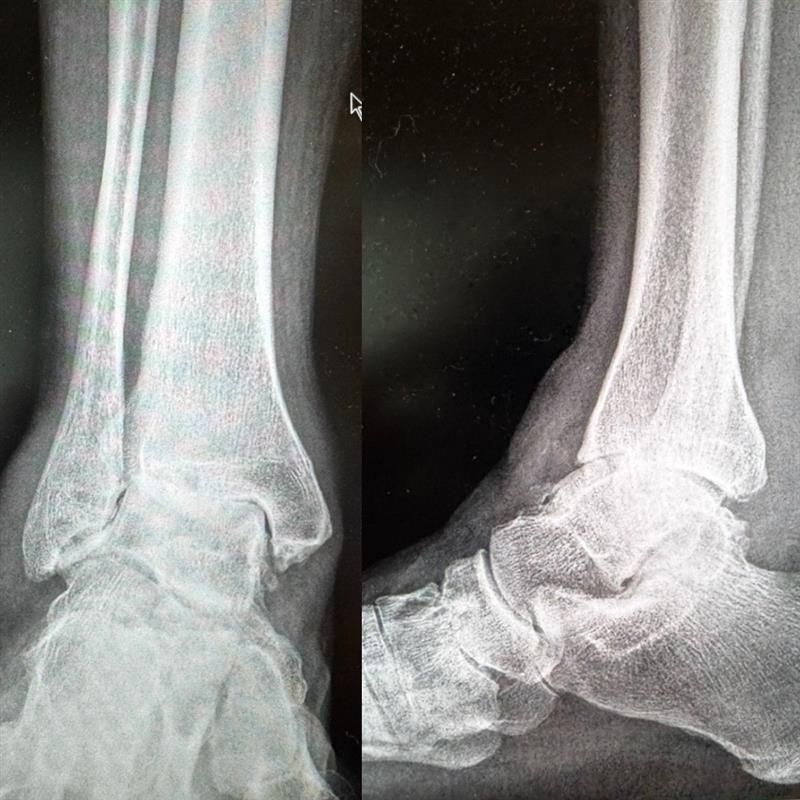

AVORS Patient Pre-OP

AVORS Patient Post-OP